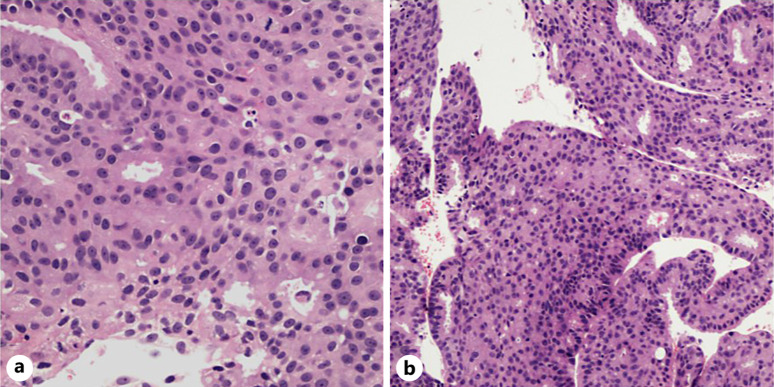

Case report: A 57-year-old woman with a history of infiltrative ductal carcinoma of the breast diagnosed 12 years earlier presented with progressive left-sided vision blurring and headaches for 3 weeks. Imaging revealed a heterogeneous lesion in the left sphenoid sinus compressing the optic nerve. The metastatic breast carcinoma with histopathological and immunohistochemical profiles matching the primary tumour was confirmed by biopsy. Because of the lesion's unresectable nature and additional metastases to the bones and lungs, palliative treatment was initiated, consisting of intensity-modulated radiation therapy and systemic therapy with abemaciclib and letrozole. After treatment, the patient's vision improved, and follow-up imaging showed reduced lesion size.